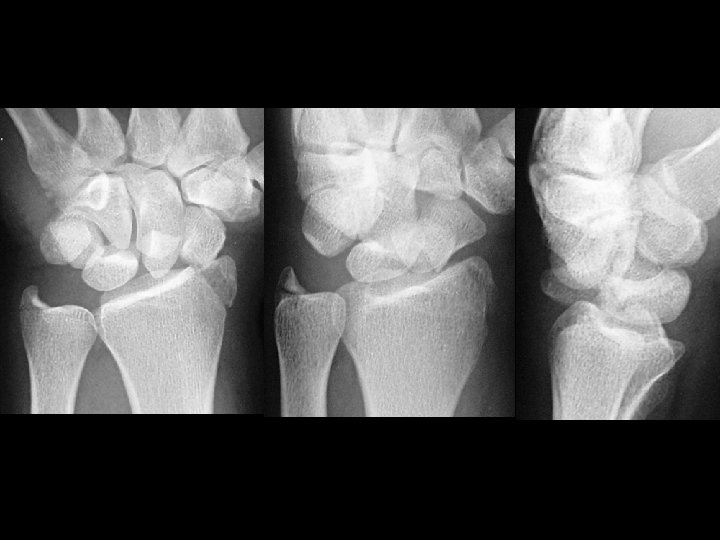

CPPD • Findings: – Bilateral wrist and 1 st – 3 rd MCP joint space narrowing – Small hook-like osteophytes of the MC heads – Chondrocalcinosis of the wrist • ddx: – hemochromotosis